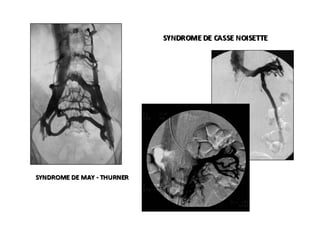

•  Hartung  O.,  chirurgien  vasculaire  français,  a  écrit  sur  44  cas  de   syndrome  de  May-­‐Thurner,  sur  lesquels,  80%  étaient  des  femmes.   •  Sandri,  10  ans  d’expérience  au  Brésil,  a  diagnos=qué  47  cas  de   syndrome  de  May-­‐Thurner,  dont  44  étaient  des  femmes.  De  la   même  manière,  il  a  diagnos=qué  49  cas  de  thrombose  ilio-­‐ phémorale,  90%  chez  des  femmes.   •  Qu’y-­‐a-­‐t-­‐il  derrière  tout  cela  ?  Est-­‐ce  une  altéra=on  hormonale  ou   exclusivement  une  altéra=on  anatomique  ?  L’altéra=on  anatomique   ne  serait-­‐elle  pas  seulement  la  cicatrice  d’une  lésion   thrombo=que  ?   •  Cela  est  un  défi  pour  moi  et  pour  la  Société  de  Phlébologie   Française.

•  Selon  l'expérience  du  chirurgien  français,  P.   Nicolini,  100%  des  cas  du  syndrome  de  May-­‐ Thurner  arrivent  à  des  femmes,  tout  comme   80%  des  thrombose  iléo-­‐fémorale.   •  Selon  l'expérience  de  Seshadri  Raju,  qui  a   traité  982  cas  de  thrombose  veineuse  iléo-­‐ fémorale  et  de  syndrome  de  May-­‐Thurner,  le   ra=o  est  de  3  femmes  pour  1  homme.